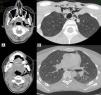

Mujer de 22 años que acude a urgencias por dificultad respiratoria y deglutoria, y dolor en hemitórax izquierdo 2h después de habérsele realizado una doble extracción dentaria. En la exploración física no se apreciaban alteraciones en orofaringe salvo la exodoncia de 2 molares superiores izquierdos, ni datos de compromiso de vía aérea superior; sin embargo, llamaba la atención la crepitación a la palpación del cuello y región superior del tórax. Mantenía estables todas las constantes vitales. Se realizó un TC facial, cervical y torácico diagnosticándose un neumomediastino que afectaba a mediastino superior y anterior, además de demostrar el enfisema subcutáneo de cuello y cara que disecaba incluso planos cervicales profundos (fig. 1). Se trató con metamizol y profilaxis antibiótica con amoxicilina-clavulánico. Fue dada de alta en 48h y revisada a las 2 semanas por cirugía torácica comprobándose la resolución completa del proceso. La aparición de neumomediastino y enfisema subcutáneo masivo, relacionados con procedimientos dentales es muy infrecuente, siendo pocos los casos documentados. Habitualmente son autolimitados sin generar compromiso vital, aunque en raras ocasiones pueden evolucionar hacia un neumotórax a tensión, mediastinitis o embolia gaseosa. El tratamiento antibiótico profiláctico está indicado sobre todo en presencia de enfermedades respiratorias subyacentes o infecciones dentales1.

A) Enfisema subcutáneo de extensión cérvico-facial disecando incluso planos cervicales profundos (fosa pterigoidea y espacios submandibular, masticador, retrofaríngeo, parafaríngeo y carotídeo izquierdos). B) Neumomediastino por extensión hacia mediastino superior (rodea tráquea, troncos supraaórticos y estructuras adyacentes) y anterior (delante del saco pericárdico y zona de salida de los grandes vasos).